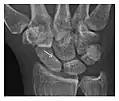

Figure 3: A 26-year-old man presenting with wrist pain after being assaulted. (a) Initial anteroposterior radiograph shows a subtle linear lucency within the scaphoid extending to the scaphocapitate articular surface that was overlooked (arrow). (b) Initial "scaphoid" view was negative. (c) Followup anteroposterior radiographs, 12 days later, shows obvious scaphoid fracture (arrows).[1]